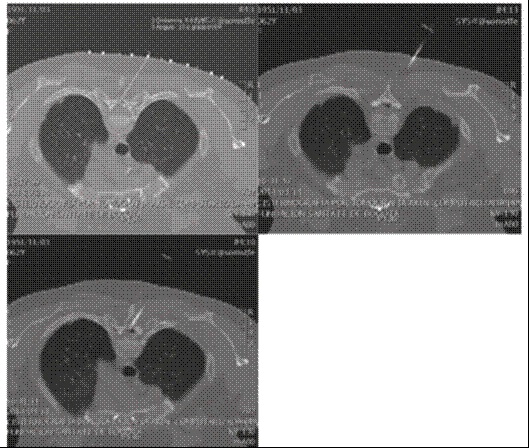

En una nueva junta multidisciplinaria se planteó que la fístula se encontraba en varios niveles por lo que no se consideró a la paciente como candidata para reparación quirúrgica y se procedió a la aplicación guiada por TAC de un parche hemático a nivel de T2; sin embargo, se observó nuevamente paso del medio de contraste al espacio subdural sin encontrar un sitio claro de comunicación de este con el espacio epidural, por lo que se suspendió el procedimiento y se optó por una mielografía dinámica guiada por TAC para detectar el sitio de la fístula; el informe fue de múltiples fístulas de líquido cefalorraquídeo a nivel de C5, C6, C7 y T1 (Figura 4) lo que descartó la posibilidad de tratamiento quirúrgico; por ello se programó nuevamente para el parche hemático.

En el quirófano y bajo guía fluoroscópica, se hizo abordaje interlaminar a nivel de T7 con aguja Tuohy nº 17 y mediante la técnica de pérdida de la resistencia con aire se identificó el espacio epidural. Se avanzó el catéter epidural hasta T2 y mediante epidurograma se confirmó la posición en el espacio epidural con adecuada migración del medio de contraste hasta C5 por lo que se procedió a la infusión de 20 mL de sangre fresca (Figura 5). La paciente tuvo mejoría completa de sus síntomas y fue dada de alta 48 horas después del procedimiento.